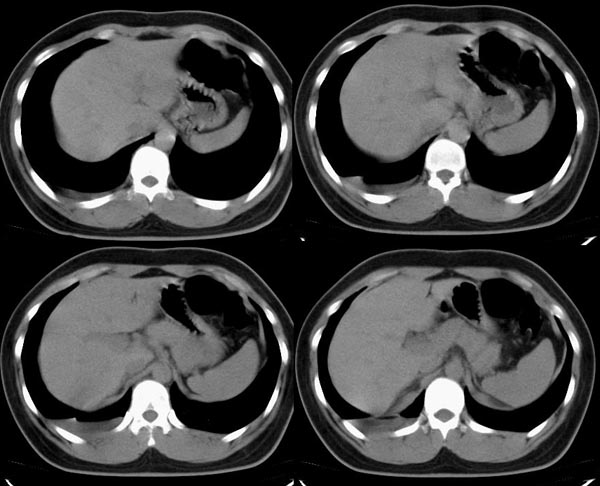

m21y既往体健,否认结核、支扩等病史;1周前患上感,无明显咳嗽,自觉无明显不适。单位体检透视时发现右侧液气胸!cr及ct如下(肺组织窗:l:-598hu w:1132hu):请大家会诊!!

右侧巨大含气囊性病变,壁薄、光整、其外侧见气体。右肺压迫性肺不张、胸腔内见少量积液。纵隔向左侧移位。左肺未见异常。诊断:1.右侧含气肺囊肿(先天性)。2.右侧液气胸。(少量液体)3.右肺压迫性肺不张。我也遇见一例这样的病人。女性。股骨外伤就诊。常规胸片发现右侧囊性病变。